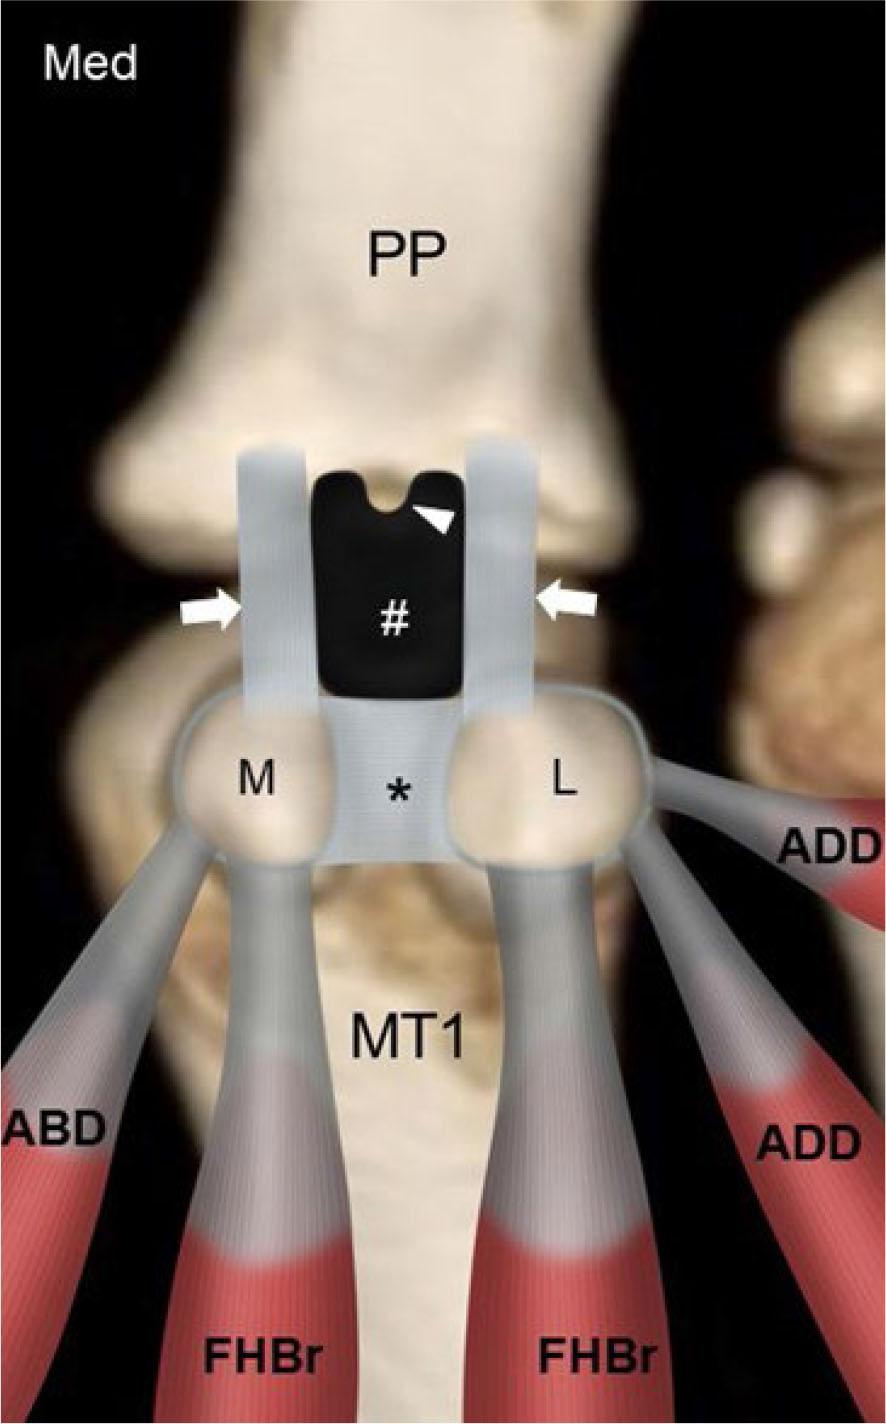

Fig. 10.

Schematic diagram plantar aspect 1st MTP joint shows the medial (M) and lateral (L) sesamoid bones held in place by the abductor hallucis (ABD), medial and lateral heads of flexor hallucis brevis (FHBr), oblique and transverse heads of adductor hallucis (ADD) tendons as well as the inter-sesamoid ligament (*) and medial and lateral sesamoid-phalangeal ligaments (arrows). The sesamoids are also supported by the paired medial and lateral metatarsal-sesamoid ligaments (not shown). The plantar plate (#) with a small distal central recess (arrowhead) is also shown. (Med, medial; PP, proximal phalanx, MT1, 1st metatarsal bone)